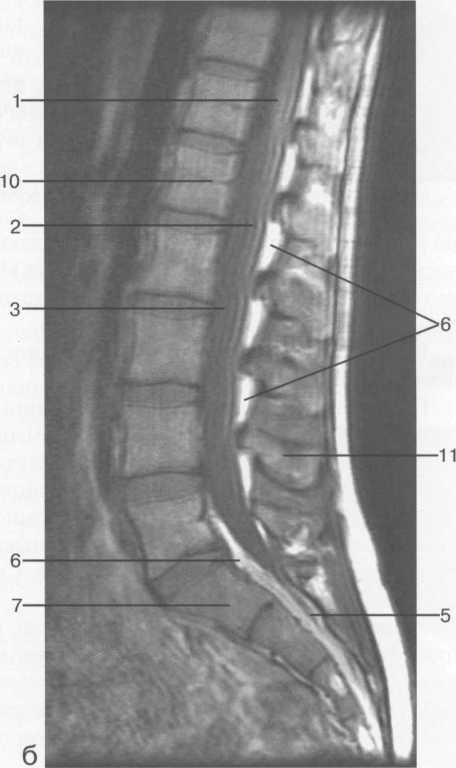

МРТ исследования дают широкую возможность исследовать  все структуры спинного мозга в разных плоскостях. ( рис. 37-41 )

Рис. 37. Срединные сагиттальные МРТ пояснично-крестцового отдела позвоночника.

а-Т2-ВИ;б-Т1-ВИ.

1 -- конус спинного мозга; 2 -- конский хвост спинного мозга; 3 -- субарахноидальное пространство; 4 -- дуральный мешок; 5 -- терминальная нить; 6 -- эпидуральное пространство; 7 -- тело Sp 8 -- пуль­позное ядро межпозвонкового диска; 9 -- фиброзное кольцо межпозвонкового диска; 10 -- каналы бази-вертебральных вен; 11 -- остистый отросток LIV.